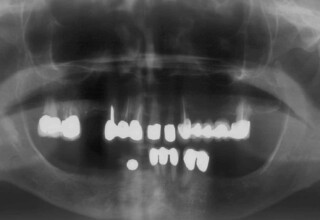

Εκτεταμένο Περιστατικό Ακίνητης Αποκατάστασης

Εκτεταμένη αποκατάσταση με στεφάνες(θήκες) σχεδόν σε όλα τα δόντια λόγω εκτεταμένων αποτριβών, παλαιών αποκαταστάσεων, οπισθίων απονευρώσεων και αισθητικών προβλημάτων. Ο ασθενής(60 ετών) παρουσίαζε έντονο βρυγμό (τρίξιμο δοντιών) που δεν είχε αντιμετωπίσει ποτέ, με αποτέλεσμα μεγάλες αποτριβές που απειλούσαν την ακεραιότητα των οπισθίων δοντιών. Οι ανασυστάσεις(σφραγίσματα) των δοντιών έγιναν κυρίως με συγκολλούμενα ρητινώδη υλικά και τρεις χυτούς άξονες ψευδοκολοβώματα. Τοποθετήθηκαν προσωρινές στεφάνες όπου εκτιμήθηκε το επιθυμητό μέγεθος, το σχήμα και η θέση των δοντιών πριν κατασκευαστούν οι τελικές μόνιμες στεφάνες.